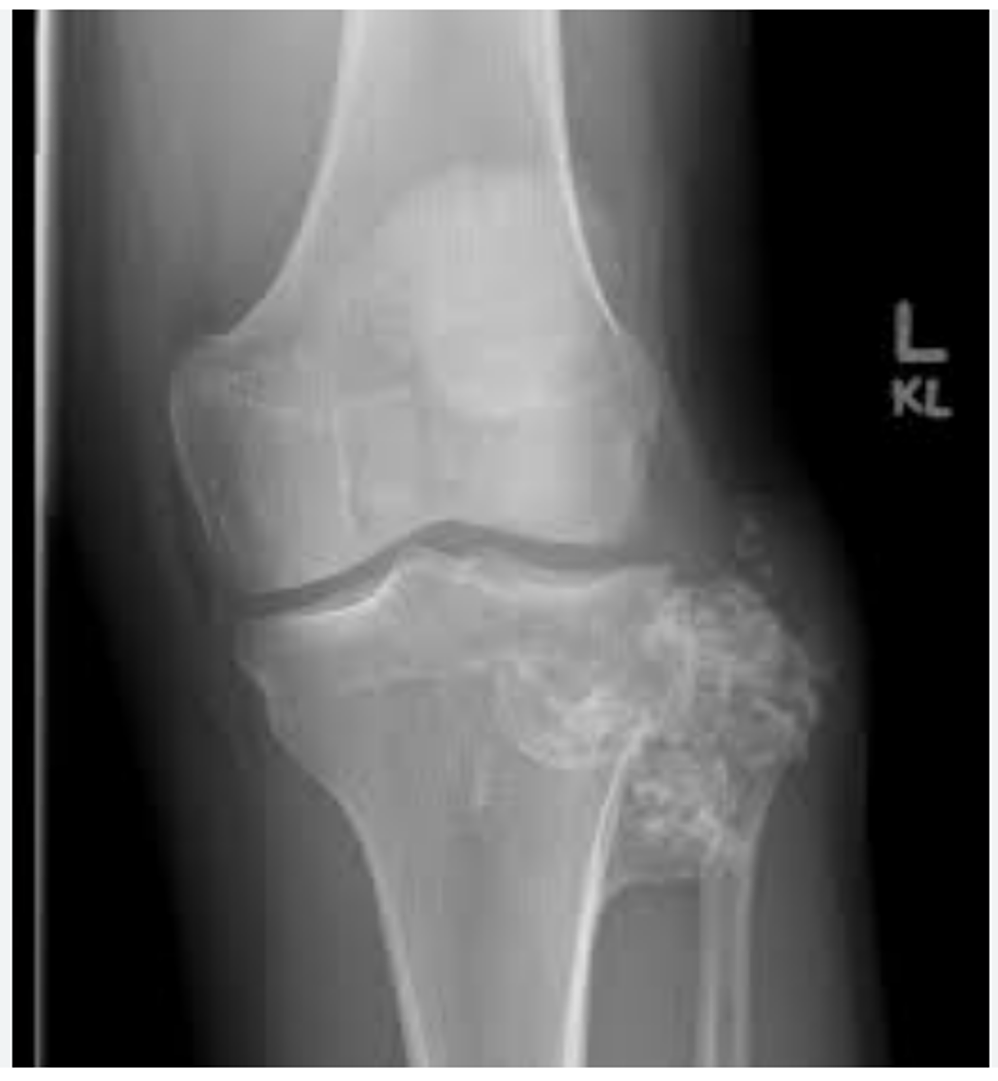

What is a chondrosarcoma?

• occurs in older patients (>40yrs)

• symptoms: pain and a lump

• many arise from previous chondromas that have undergone malignant change

• x-ray: ‘fluffy popcorn’ calcification